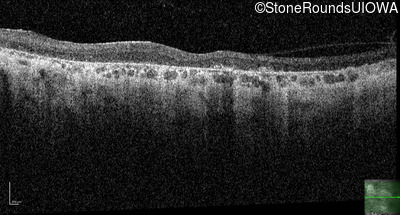

OCT Stack

MCL

KIF11

Lys157Stop AAA>TAA

AD